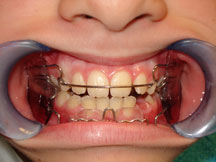

Ortodonzia pubblica

Il trattamento ortodontico è suddivisibile in Ortodonzia intercettiva e dell'età adulta in base al grado di sviluppo scheletrico del paziente.

La terapia intercettiva ha lo scopo di correggere disarmonie di natura prevalentemente scheletrica che, se non trattate tempestivamente, possono evolvere ed aggravarsi nel corso del tempo. I dispositivi ortodontici possono essere di tipo rimovibile o fisso in base alle singole fasi terapeutiche.

Nel caso in cui le problematiche scheletriche non dovessero essere state intercettate durante le fasi di crescita il paziente necessita di trattamento ortodontico-chirurgico atto alla correzione completa dei difetti sia scheletrici che dentali.

Presso i nostri centri è disponibile il servizio specialistico di ortodonzia pubblica rivolto a pazienti in che presentano gravi dismorfie osse che vanno trattati con terapia intercettiva prima o con terapia ortodontico-chirurgica poi.

![]() | ![]() |